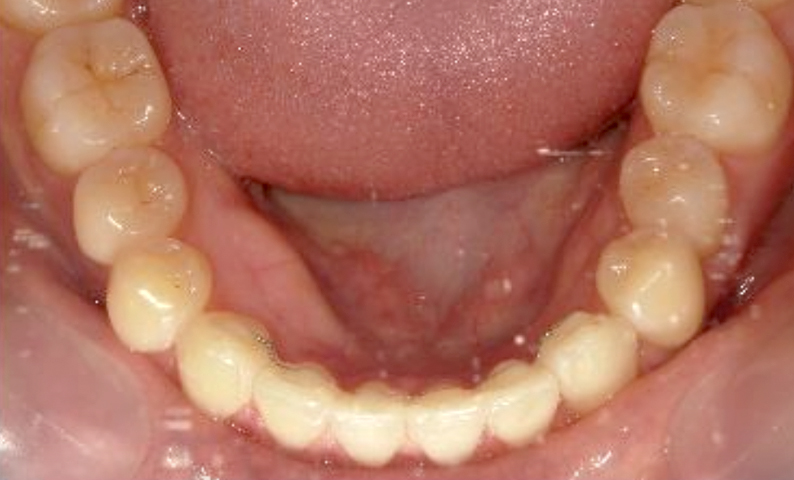

| 治療前 | 治療後 |

|---|---|

|